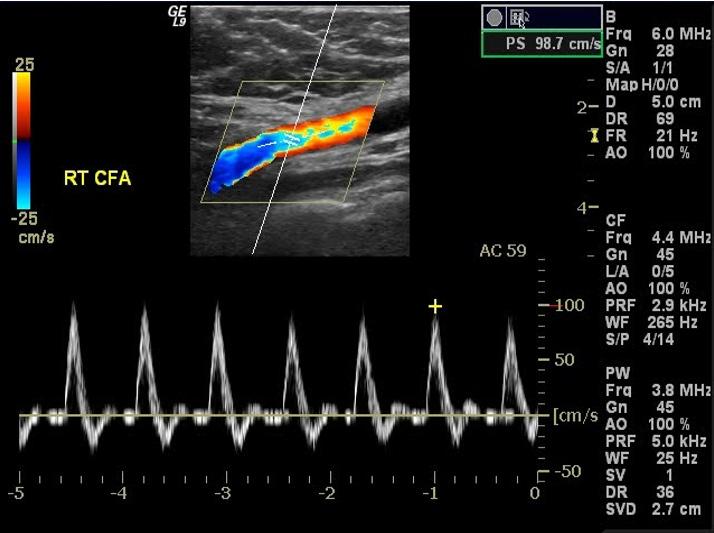

Positivo (≥ 500 ng / ml): posible TVP → Proceda a la ecografía doppler Ecografía doppler o de compresión

♦ Prueba de elección (ideal) para confirmar el diagnóstico (ENAM 2020, ENAM EXTRA 2021)

♦ Resultados

Positivo: confirma TVP

– No compresibilidad de la vena obstruida (hallazgo + importante)

Masa intraluminal hiperecoico (trombo)

– Distensión de la vena afectada

Aumento inadecuado del flujo venoso en la compresión distal de la pantorrilla o maniobra de Valsalva